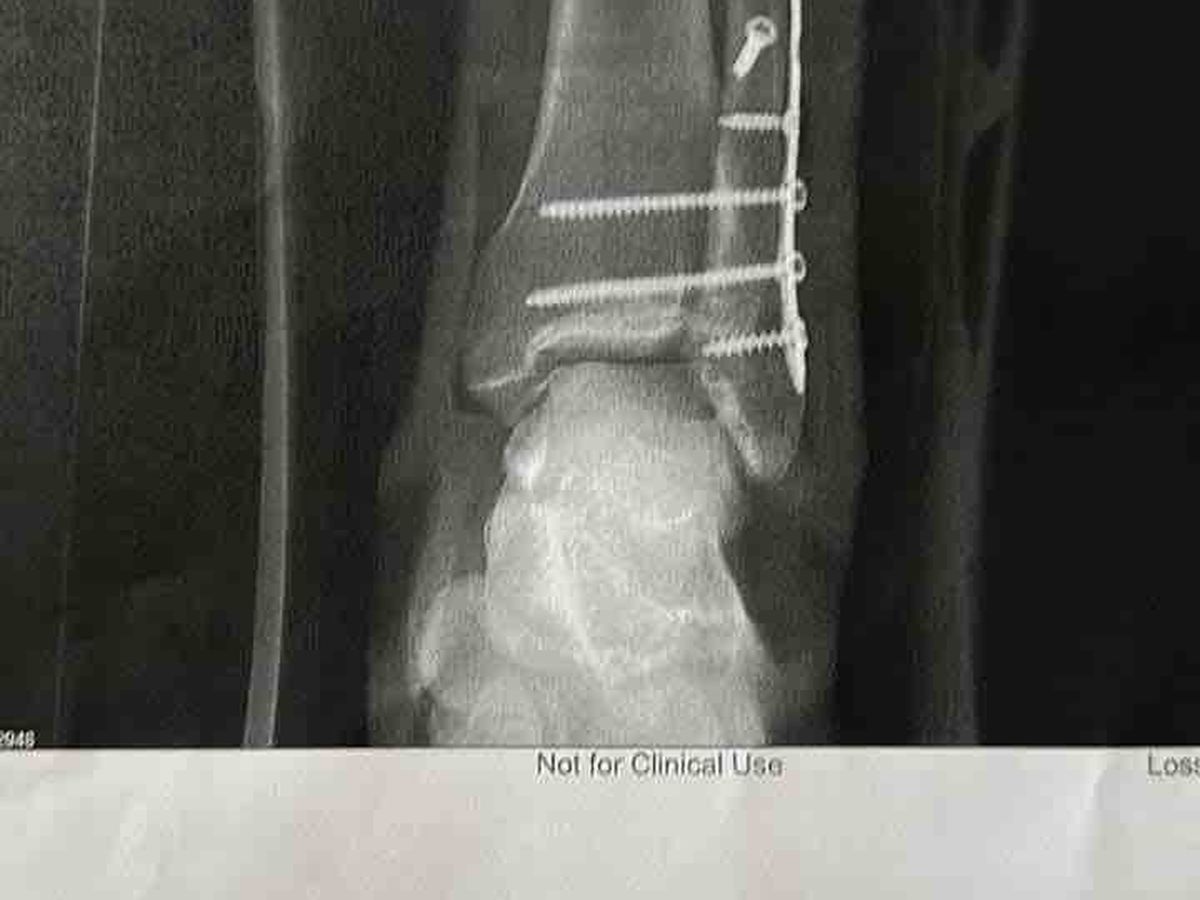

Yesterday (July 1st) went a little different than we had originally planned…. We were at a trampoline park having a great time when Gage Pulley decided to show Steel some more flips. He had been flipping and jumping on the trampolines the whole time we were there. He went to do a front flip, landed wrong and I heard the crack. He broke his tibia in half, broke the bottom half of his fibula and dislocated his tibular joint. His foot was hanging to the side but he took it like a freaking champ. I don’t know how he stays so calm. We finally made it home around 2 this morning. It’s been a long night. He’s in a lot of pain and will have to have surgery within the next week or so and be out of work for at least 6 weeks.

Non weight bearing for 6-8 weeks